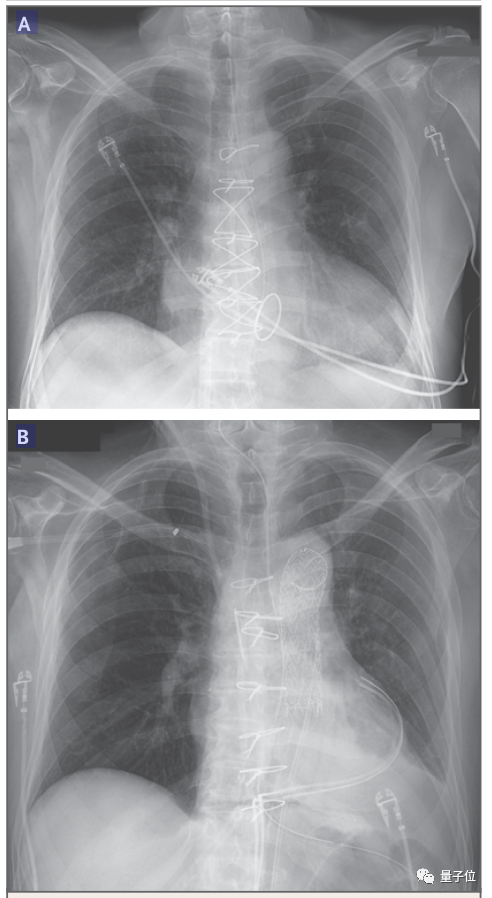

△图B中患者心脏增大

论文中表明,患者死后心脏重量几乎增加了一倍,从328克增长到600克。

最为明显的现象,就是心脏的重量几乎翻了一番。医生解释,这主要是因为血管出现了渗漏的迹象。

不过紧接着,他的情况就急转直下,检测发现移植心脏的心脏壁异常肥大、心室体积缩小,体内对猪组织的抗体水平也在不断升高。